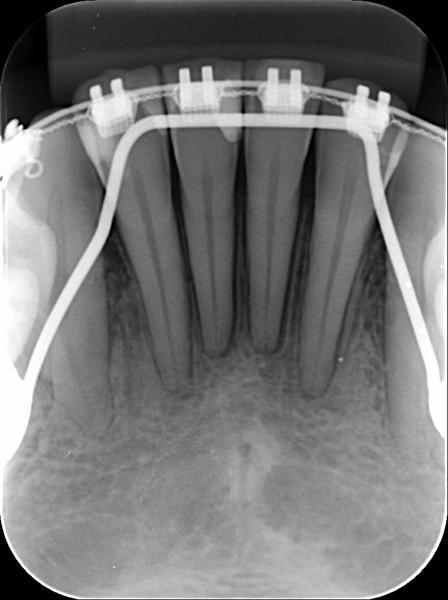

Radiografia Oclusal